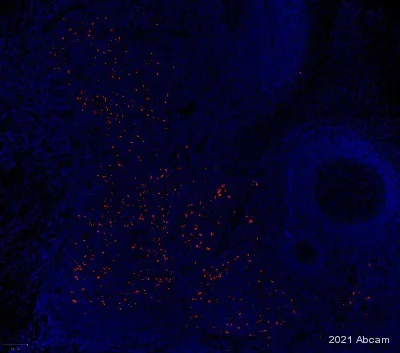

Immunohistochemistry (Formalin/PFA-fixed paraffin-embedded sections) analysis of Human liver cancer labelling CD208 with ab281573 at 1/1200 (B), CD3E with ab237707 at 1/1200 dilution (C) and CD19 with ab237772 at 1/1200 dilution(D). Opal Polymer HRP Ms + Rb was used as a secondary antibody, and DAPI was used for a nuclear counter stain. Heat mediated antigen retrieval with Tris-EDTA buffer (pH 9.0, epitope retrieval solution2) for 20 mins.

Panel A : merged staining of anti-CD208 (red; Opal™570), anti-CD3E (green; Opal™520) and anti-CD19 (magenta; Opal™690) on human liver cancer.

Panel B : anti-CD208 staining dendritic cells in human liver cancer.

Panel C : anti-CD3E staining T lymphocytes in human liver cancer.

Panel D : anti-CD19 staining B lymphocytes of human liver cancer.

The section was incubated in three rounds of staining : in the order ab281573, ab237707, and ab237772 for 30 mins at room temperature. Each round was followed by a separate fluorescent tyramide signal amplification system.

The immunostaining was performed on a Leica Biosystems BOND® RX instrument with an Opal™ 4-color kit. Image acquisition was performed with Leica SP8 confocal microscope.